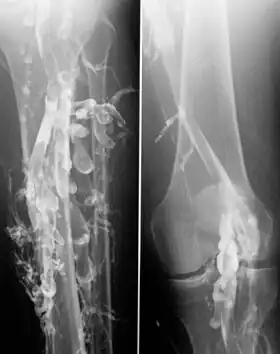

Venography in a patient with deep vein thrombosis

Contrast venography is the gold standard for judging diagnostic imaging methods for deep vein thrombosis; although, because of its cost, invasiveness, and other limitations, this test is rarely performed.[1]

Venography can also be used to distinguish blood clots from obstructions in the veins, to evaluate congenital vein problems, to see how the deep leg vein valves are working, or to identify a vein for arterial bypass grafting.